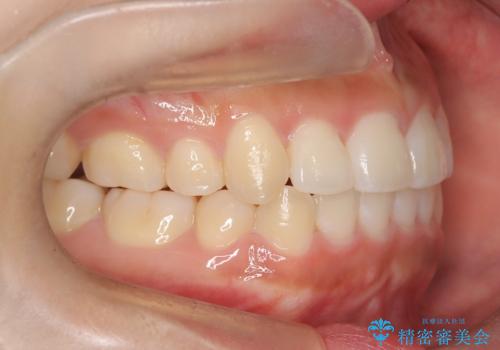

- 前歯のでこぼこが気になると来院されました。

奥歯の噛み合わせは綺麗に噛んでいたため、前歯の叢生(でこぼこ)を、短期間で治療完了するように計画しました。